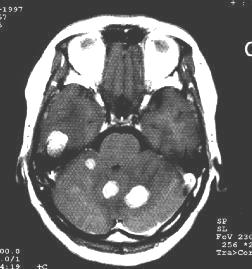

2.局部症狀:由於腫瘤對腦的損害較重,並且常為多發,局部症狀多顯著,且累及範圍較廣。依腫瘤所在部位產生相應的體徵。40%以上病人有偏癱、約15%有偏側感覺障礙,約10%有失語,5%左右有偏盲。位於小腦者則有眼球震顫、共濟失調等,亦可有後組顱神經症狀。

3.CT掃描:不但可定位,並可顯示腫瘤的大小、形狀及腦組織、腦室的改變、特別易於發現多發性腫瘤、腫瘤類圓形或形狀不規則,呈高密度或混雜密度影像,混雜密度者常為腫瘤內有壞死囊變,則顯示有低密區。強化後大多有明顯的塊狀或環狀影像增強、腫瘤周圍常有低密度腦水腫帶。可見腦室受壓變形,小腦腫瘤可見第三腦室以上對稱擴大。